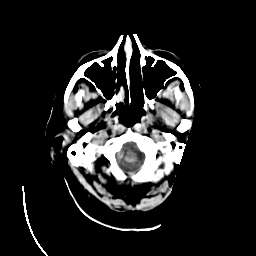

CT Study #3 -- Slice #2